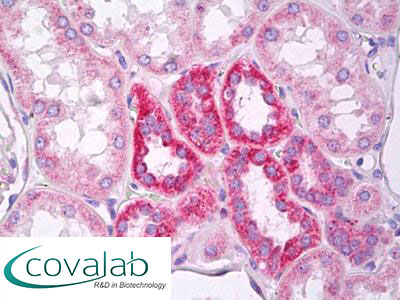

Anti-MARK2 antibody IHC staining of formalin-fixed, paraffin-embedded human kidney tubules after heat-induced antigen retrieval.